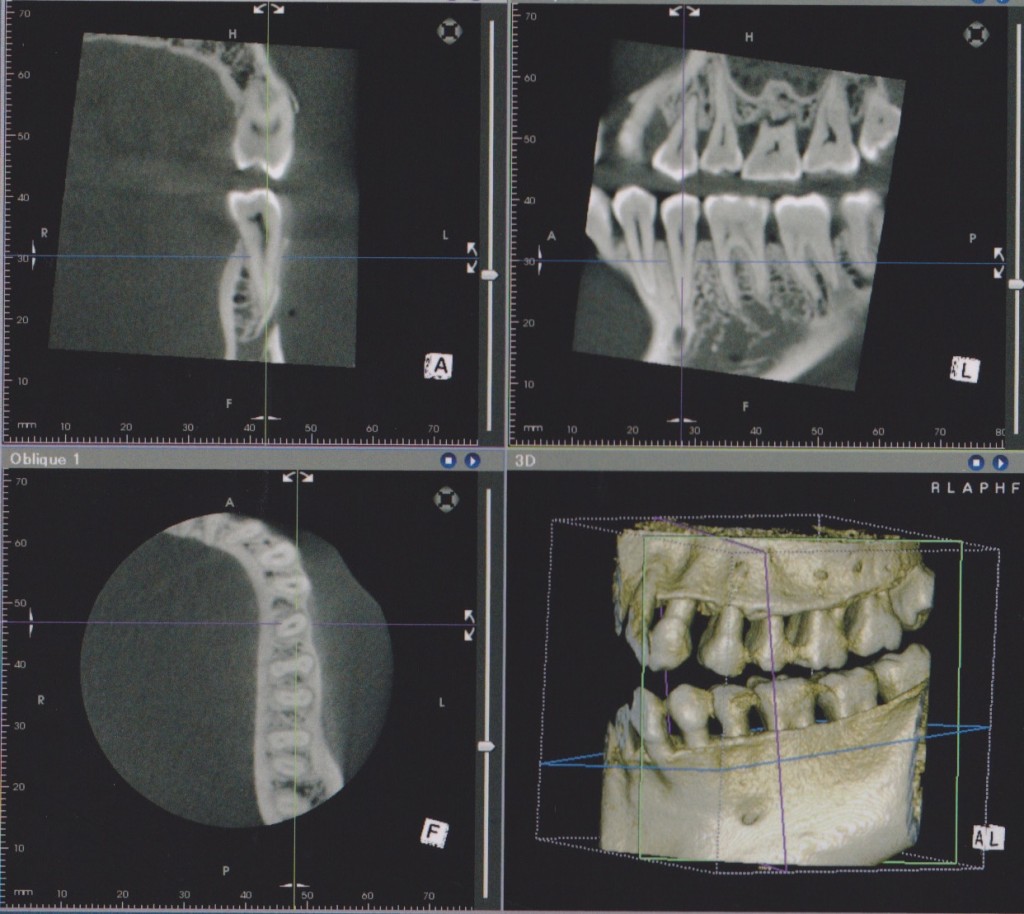

エックス線CT診断装置を導入いたしました。

この装置は今までの平面的なレントゲン写真ではなく、立体的に撮影し必要な場所の断面を見ることのできるものです。特に歯の神経の処置や歯周病の治療において歯の周囲の顎骨の様子が手に取るようにわかり、確実な診断の助けになります。

また今日は、より正確なCT診断のための講習会に参加してきました。CTの原理から読影の注意点までとても参考になりました。より良い治療のためのとても重要な診断装置であるとの確信を深めました。